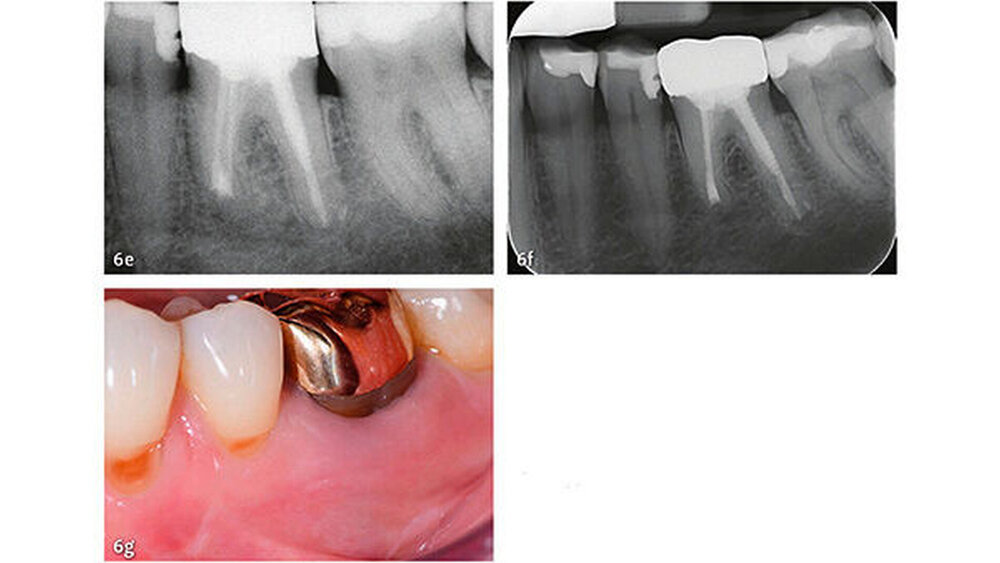

Klinische Studien

Die wesentlichen Daten von klinischen Studien über die Anwendung von MTA als retrogradem Füllmaterial sind in Tabelle III zusammengefasst. Die erste klinische Studie mit Auswertung der Erfolgsrate nach MTA-Anwendung in der apikalen Chirurgie wurde von Chong et al. (2003) publiziert - es war auch gleich die erste randomisierte Studie, welche MTA mit einem anderen retrograden Verschlusszement untersucht hat. Generell zeigen alle klinischen Studien sehr hohe Erfolgsraten für MTA in der apikalen Chirurgie (83,7% bis 96%). Die von uns 2014 publizierten Langzeitdaten (5 Jahre Beobachtungsdauer für alle behandelten Zähne) mit einer Erfolgsrate von 92,5% deuten auf eine sehr gute Stabilität und auf ein hohes Abdichtungsvermögen von MTA (von Arx et al. 2014) (Abb. 4 und 5).

Die Dokumentation der 10-Jahresdaten ist im Gange, und die bisherige Analyse deutet auf eine konstant hohe Erfolgsrate auch nach zehn Jahren (Abb. 6). Eine systematische Auswertung mit Meta-Analyse aller bis 2007 publizierten retrograden Füllmaterialien in Vergleichsstudien mit mindestens zwei getesteten Verschlussmaterialien ergab für MTA die höchste Wahrscheinlichkeit einer periapikalen Ausheilung (91,4%) (von Arx et al. 2010a).